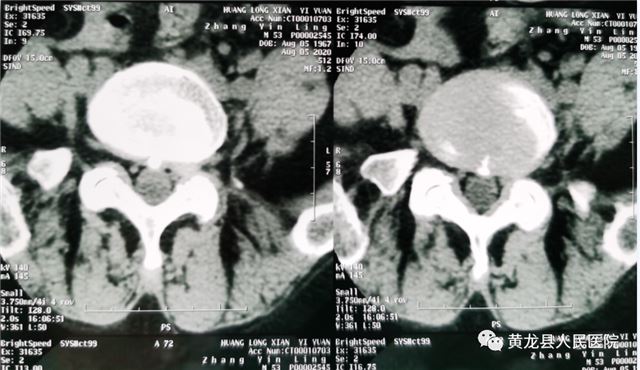

张某,女,52岁,近1月来,出现腰部疼痛,反复发作,并向左侧下肢放射,劳累后加重,休息后减轻,无法正常行走,严重影响生活质量,在家人陪同下来到黄龙县人民医院外科就诊。恰逢唐都医院骨科帮扶支援专家高全有副主任医师门诊坐诊,首诊详细了解患者病史,经仔细查体,结合影像学检查,最终诊断为:腰椎间盘突出症(L5-S1)。

术前CT检查